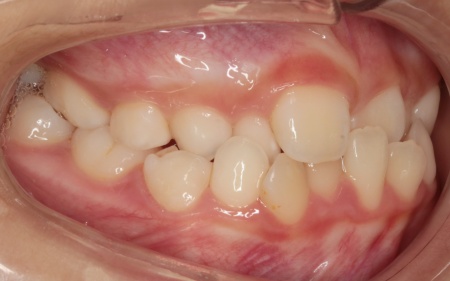

10歳女の子 顎の幅を広げる装置とマウスピース型の矯正装置で反対咬合を改善した症例

拝見したところ、上前歯が下前歯の内側に入り込む「反対咬合(こうごう)」が認められました。

詳しい検査の結果、患者様の反対咬合は歯の位置の問題ではなく、上顎の発育が十分ではないことが主な原因と考えられます。